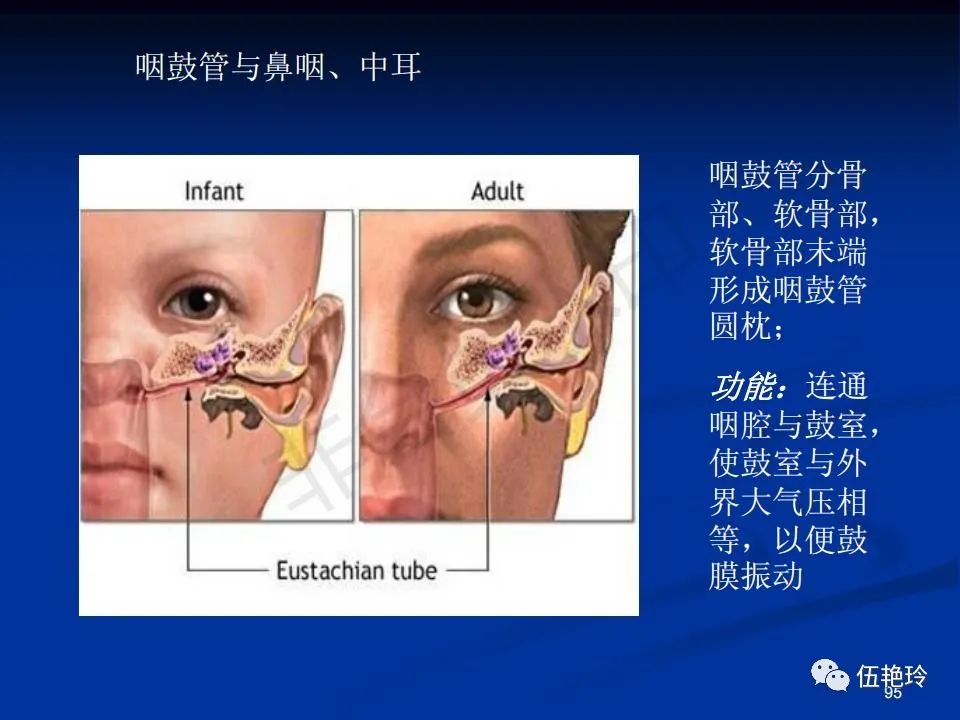

耳与面神经的解剖